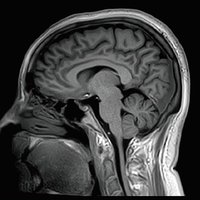

Der Vantage Galan 3T von Canon Medical Systems bietet Ihnen und Ihren Patienten eine neuartige Erfahrung in der Magnetresonanztomographie. Der Vantage Galan 3T legt sein Augenmerk auf das positive Patientenerlebnis, eine hohe Bildqualität und einfache klinische Arbeitsabläufe.

KI-optimiertes Arbeiten und modernste 3T-Technologie machen den Vantage Galan 3T von Canon Medical aus. Canons KI-Anwendung AiCE, kurz für Advanced intelligent Clear-Imagequality Engine, entfernt intelligent das Rauschen und führt zu einer Verbesserung des SNR (Signal-Rausch-Verhältnis). Mit Hilfe der Deep Learning Technologie gelingen besonders klare und deutliche Bilder. Insgesamt ermöglicht die KI-Unterstützung des Vantage Galan 3T somit nicht nur eine höhere Auflösung der Bilder, sondern verkürzt in vielen Fällen auch die Aufnahmezeit.